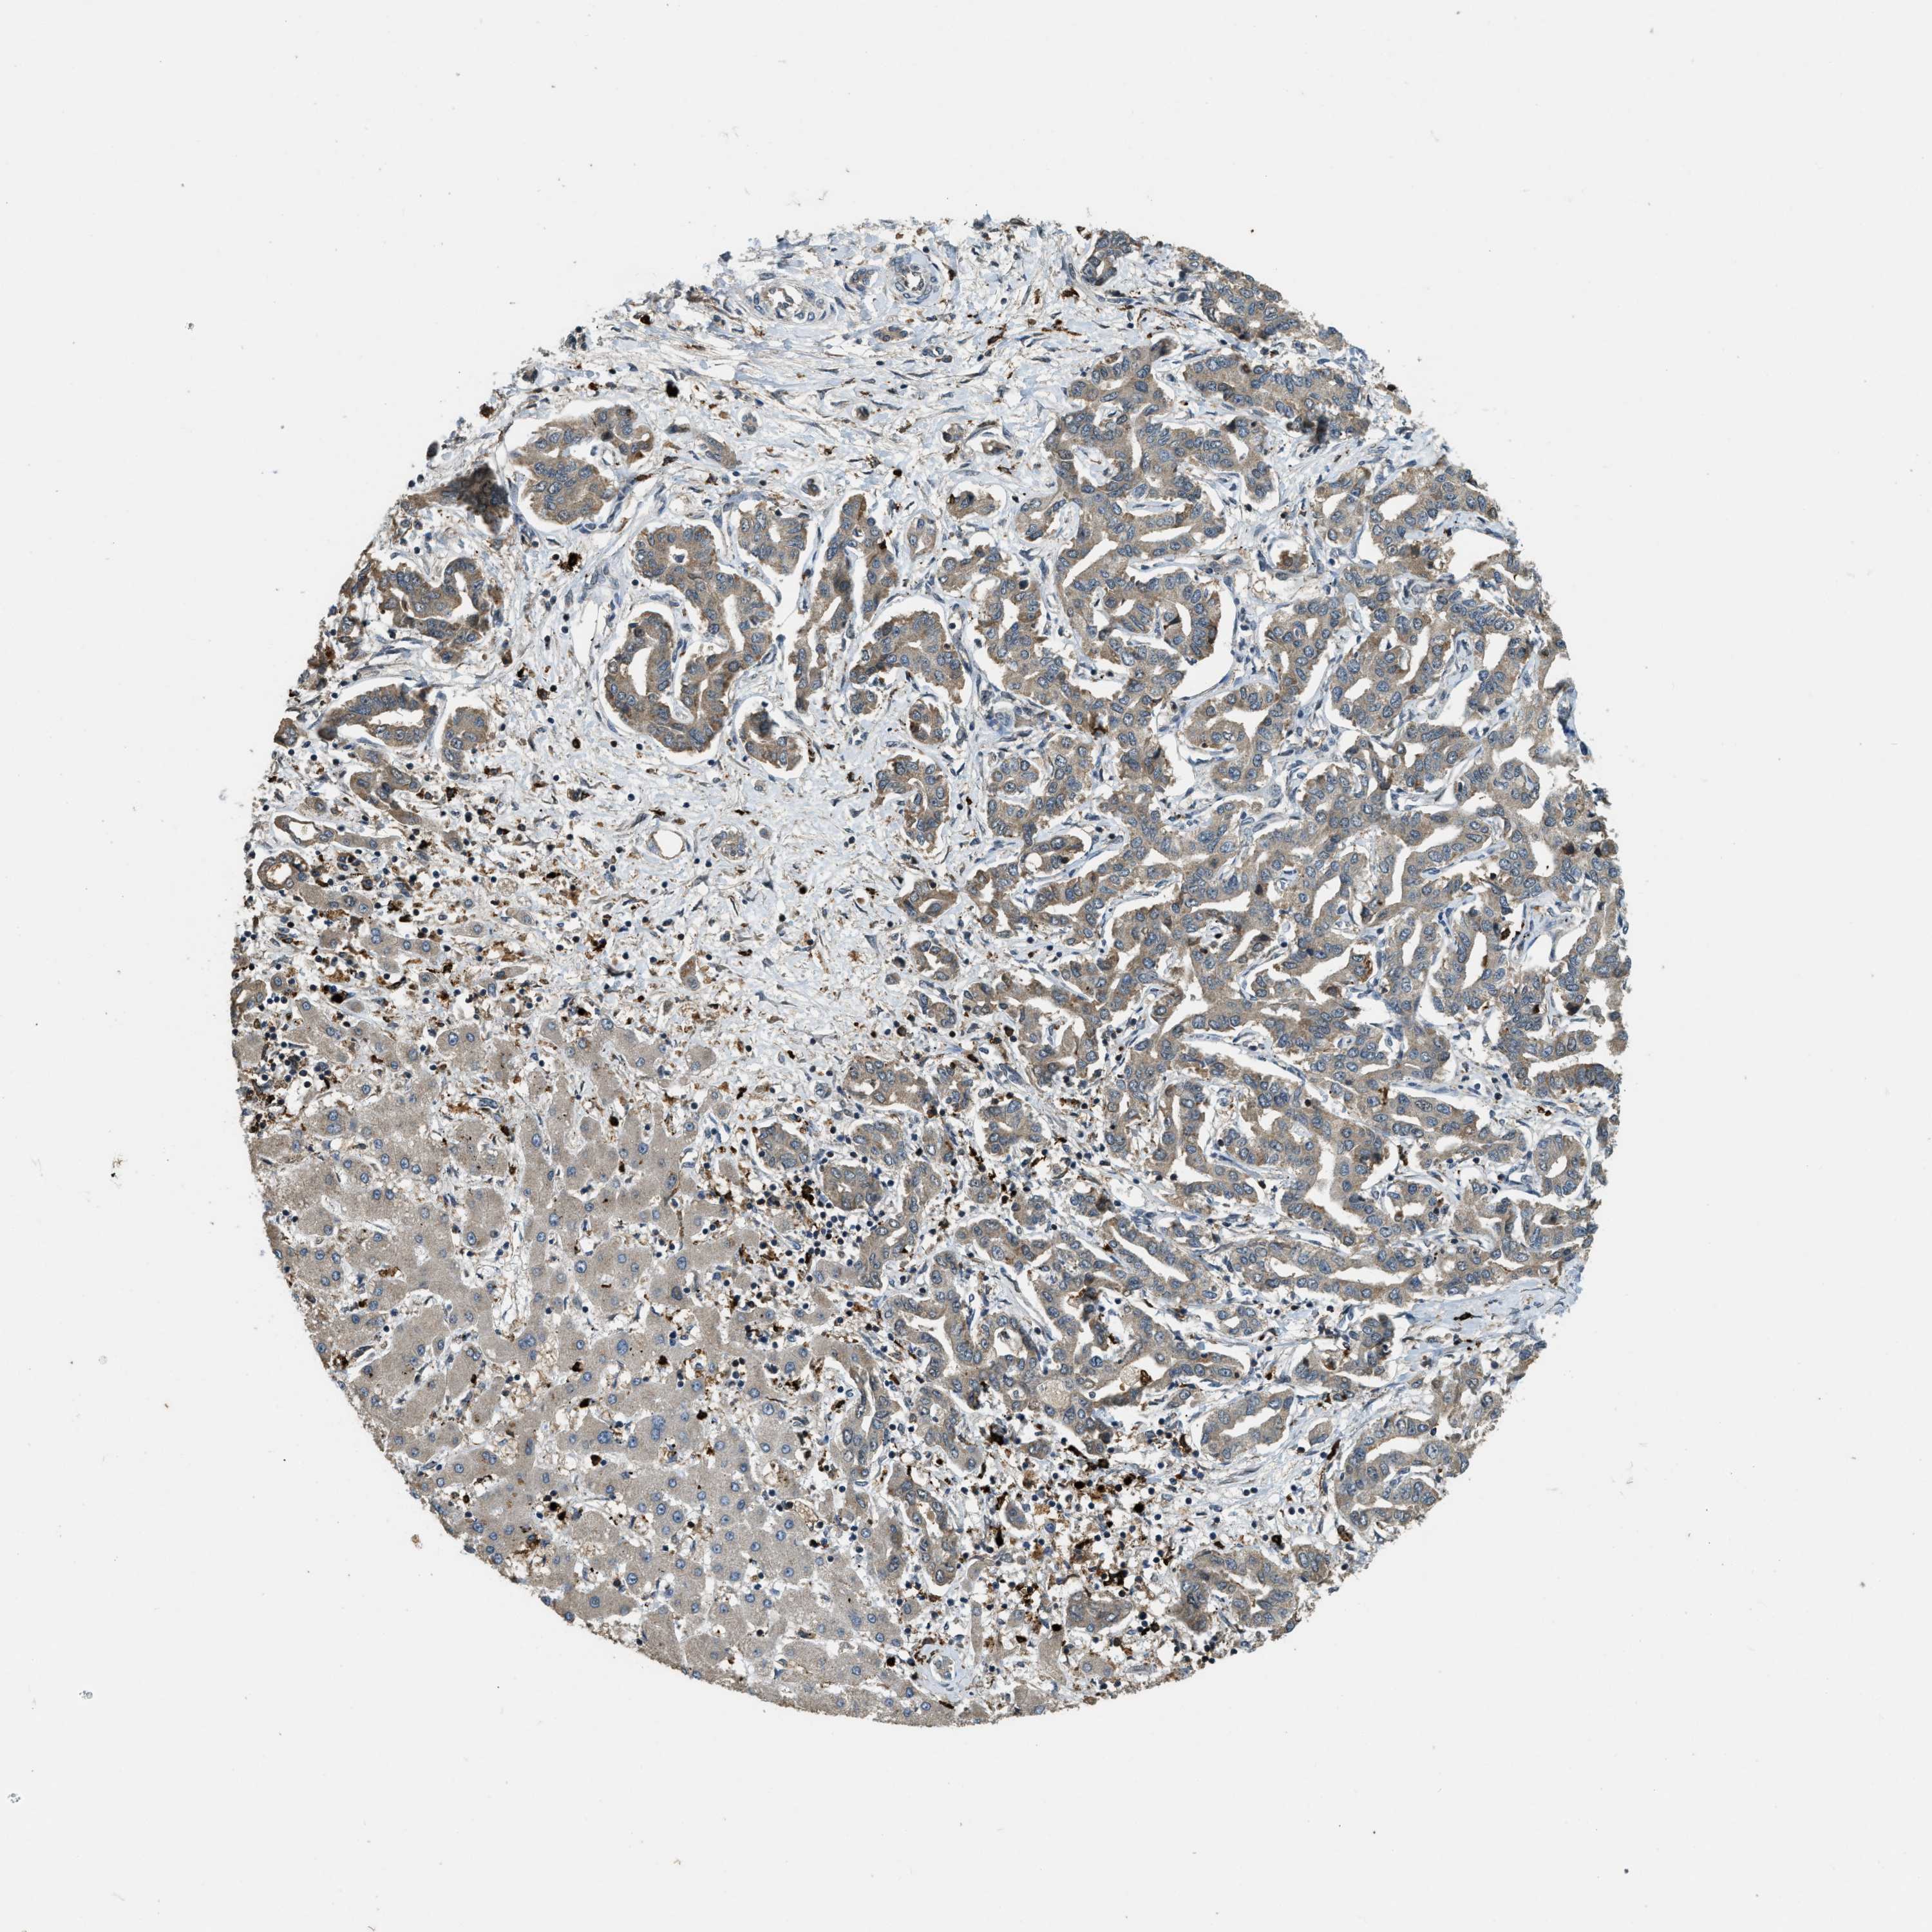

LIVER CANCER - Protein expressioni

A mouse-over function shows sample information and annotation data. Click on an image to view it in a full screen mode. Samples can be filtered based on level of antibody staining by selecting one or several of the following categories: high, medium, low and not detected. The assay and annotation is described here.

Note that samples used for immunohistochemistry by the Human Protein Atlas do not correspond to samples in the TCGA dataset.

Antibody stainingi

Antibody staining in the annotated cell types in the current human tissue is reported as not detected, low, medium, or high, based on conventional immunohistochemistry profiling in selected tissues. This score is based on the combination of the staining intensity and fraction of stained cells.

Each image is clickable and will lead to virtual microscopy that enables deeper exploration of all samples and also displays staining intensity scores, fraction scores and subcellular localization as well as patient and tissue information for each sample.

Antibody HPA018133

Staining

High

Medium

Low

Not detected

Intensity

Strong

Moderate

Weak

Negative

Quantity

>75%

75%-25%

<25%

None

Location

Nuclear

Cytoplasmic/membranous

Cytoplasmic/membranous,nuclear

Cholangiocarcinoma

Carcinoma, Hepatocellular, NOS